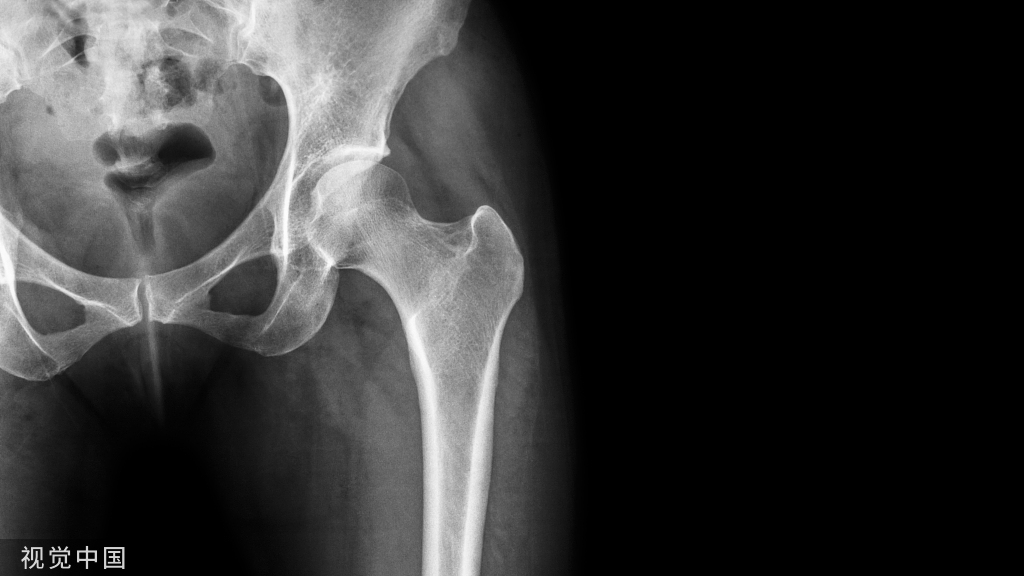

5. 髋部疼痛:

(点击图片放大查看)